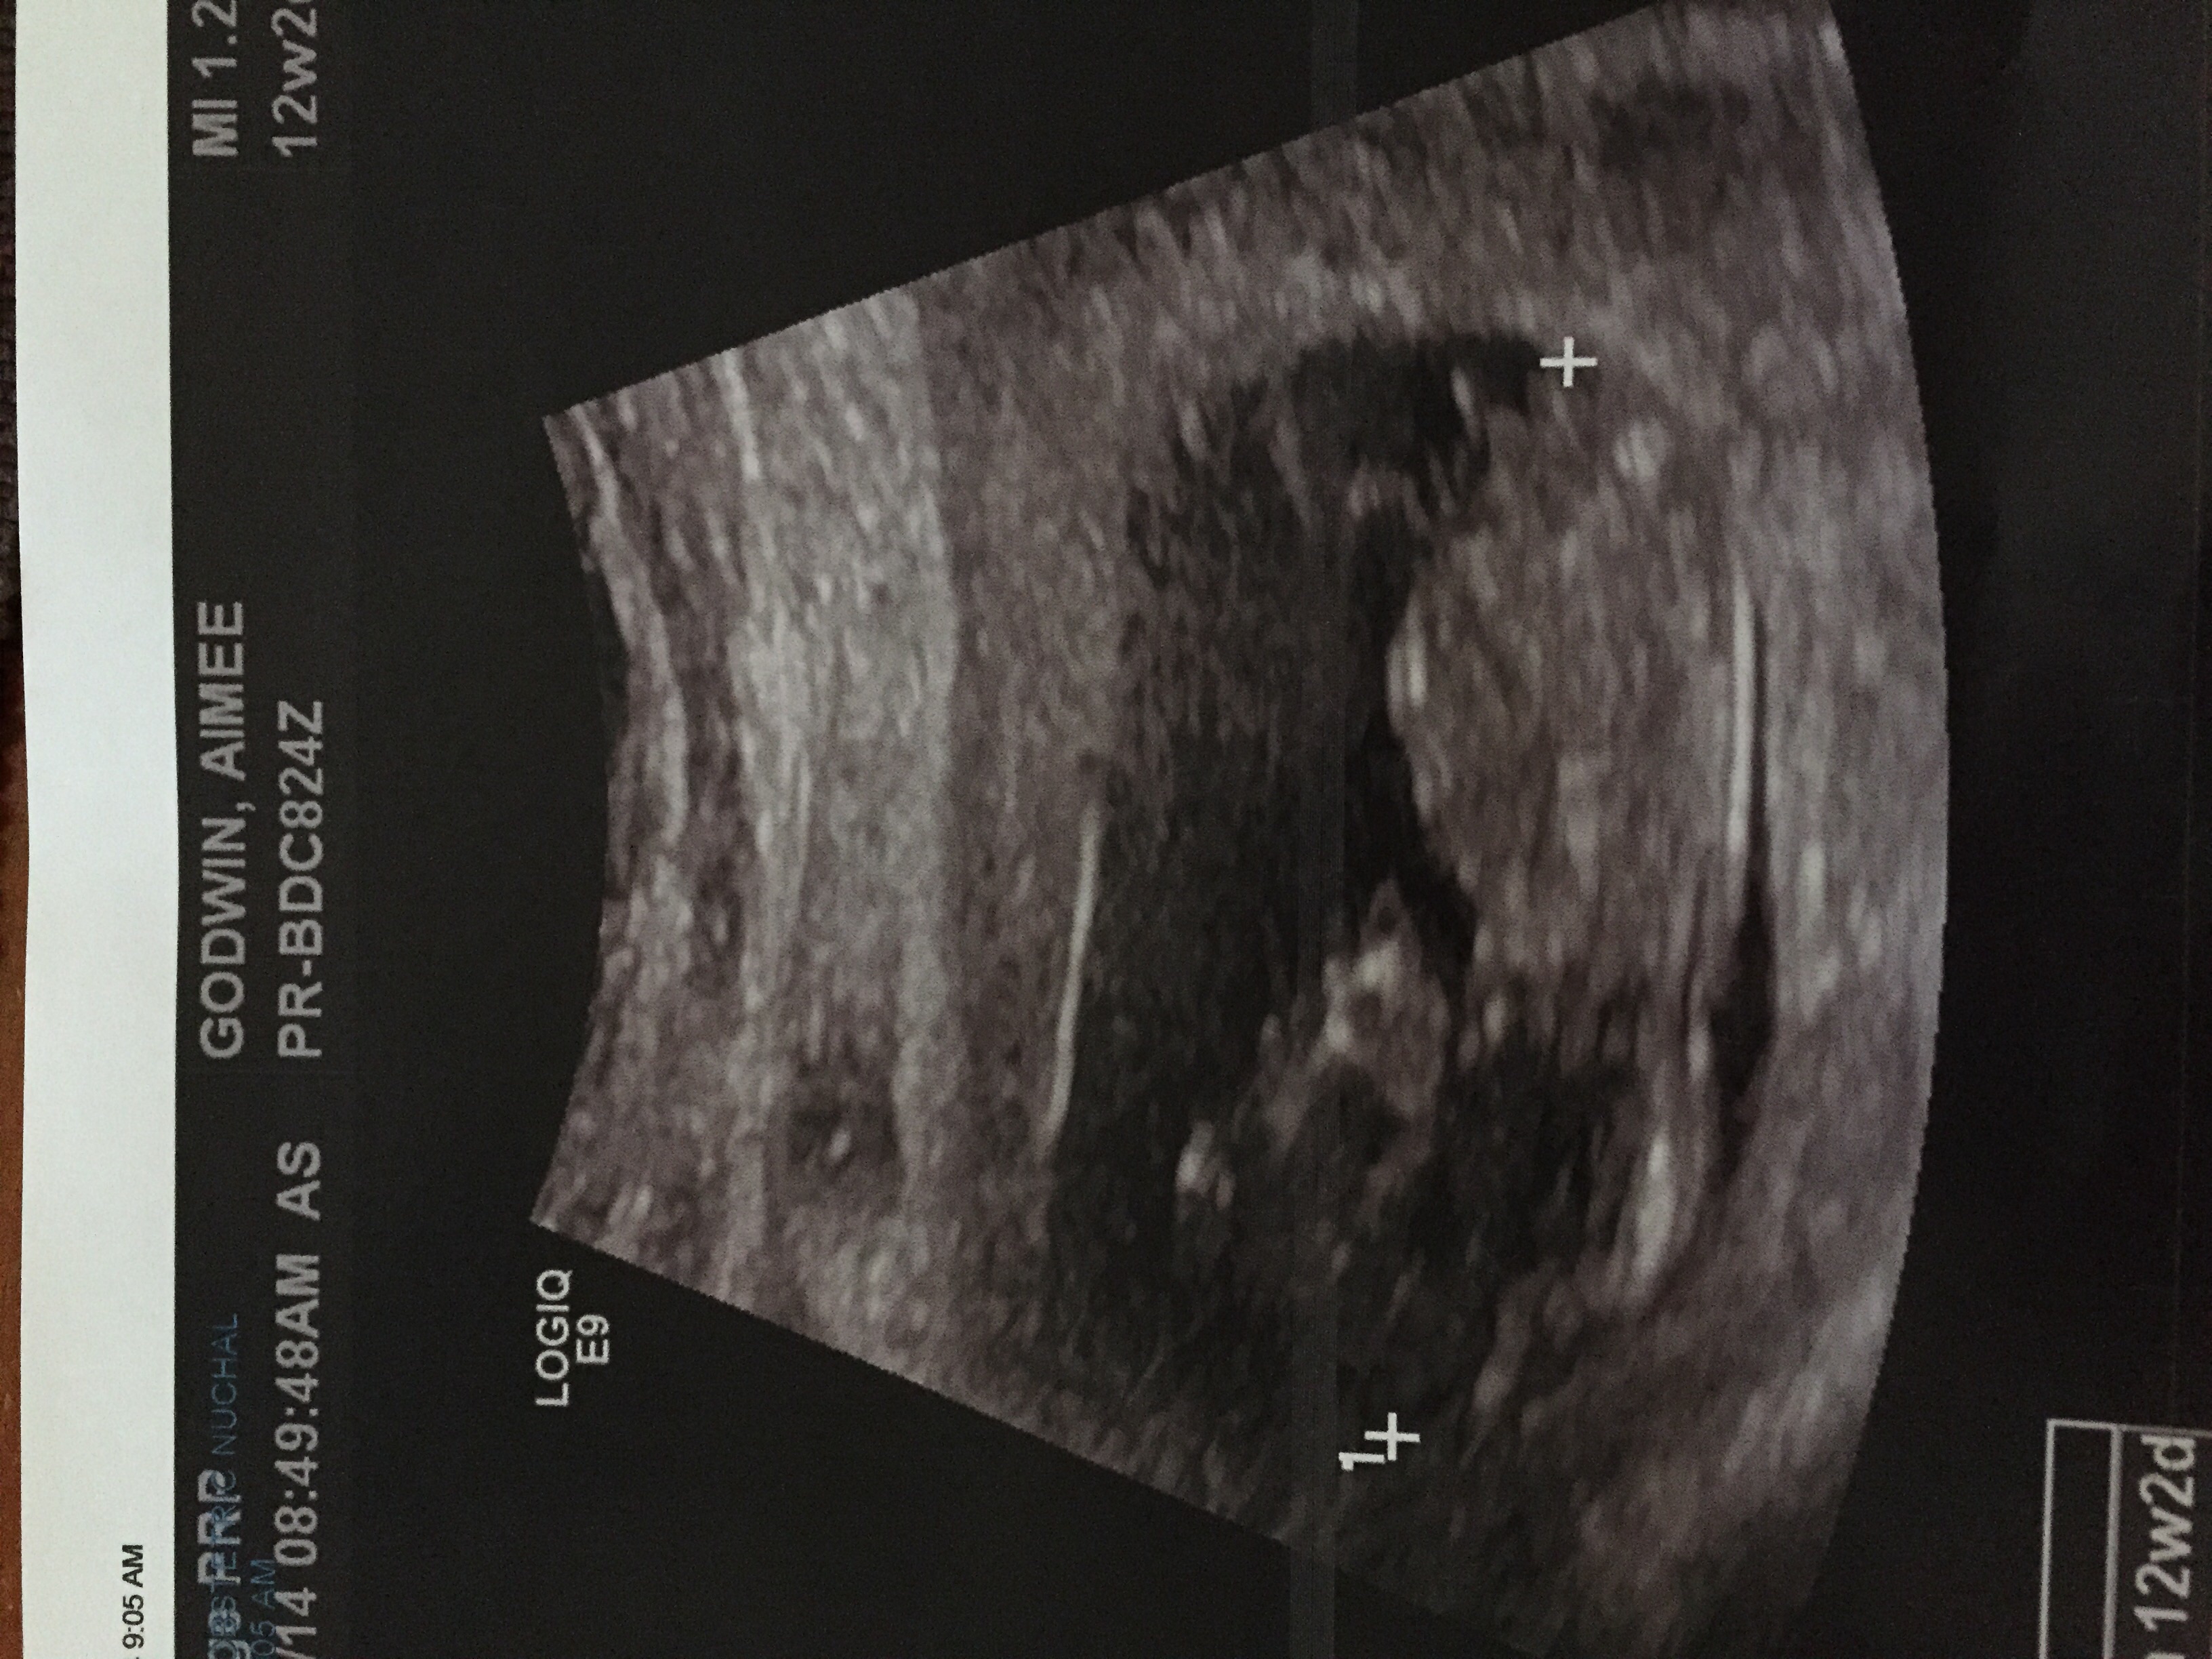

I'm not to sure on what I'm looking at lol is it just up from the cross?

Where is the nub?

Boy. Its that angled long white line sticking up a little above the cross.

Also when I had the ultrasound done I asked the lady if it was that white line and she said no that was the umbilical cord

Alot of them will tell you that because of liability reasons. Its POSSIBLE. I cannot see your whole cord but this highlighted part is the part I know for sure is your cord.Attachment 23306